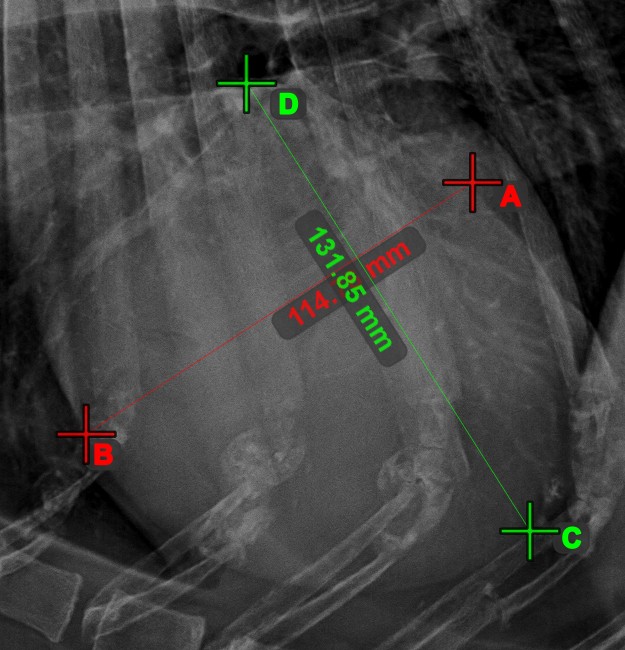

Linienmessung¶

Erstellen Sie eine Linienmessung, um den Abstand zwischen zwei Punkten mit hoher Genauigkeit zu berechnen.

Wählen Sie das Werkzeug Linienmessung aus und weisen Sie es einer der verfügbaren Maustasten zu. Setzen Sie die Start- und Endpunkte in der Szene oder wählen Sie sie aus bereits vorhandenen Punkten im Bild aus. Der Abstand zwischen den beiden Punkten wird automatisch anhand der Standardkalibrierdaten oder der durch die Längenkalibrierung-Messung neu kalibrierten Daten berechnet.

Ändern Sie den Start- und Endpunkt mit dem Werkzeug Objekt auswählen/verschieben. Der Abstand zwischen den beiden Punkten wird automatisch neu berechnet.